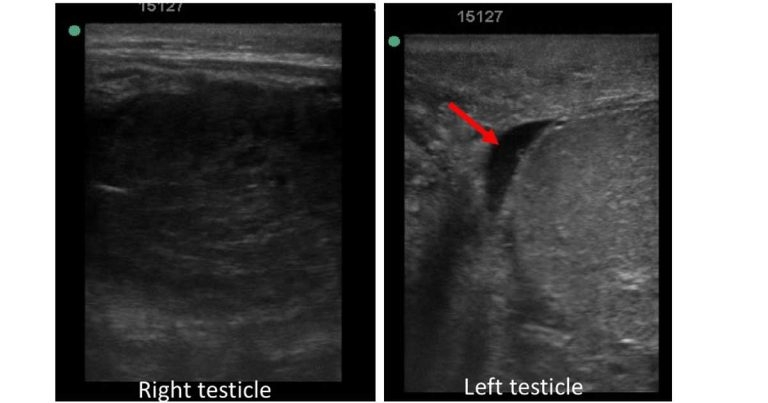

Figure 2. Comparison of echogenicity of the testicular parenchyma of the right and left testicles. Note a small amount of hypoechogenic free fluid within the vaginal tunic on the left side (red arrow).

Ultrasonographic examination of the scrotum using a 7.5MHz linear probe was then performed. The right testicular region had a small amount of free fluid within the vaginal tunic and marked heterogeneous hypoechogenicity of the testicular parenchyma (Figure 2).

Evaluation of the left testicular region revealed normal (homogenous and relatively hyperehoic) echogenicity of the testicle compared with the right and a small amount of free fluid within the vaginal tunic (Figure 2). No other abnormalities were noted.